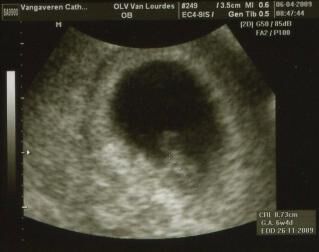

Klik hier om een link te hebben waarmee u dit artikel later terug kunt lezen.Eerste ontmoeting

Klik op de afbeelding om de link te volgen Alweer een grote dag in ons bestaan. We hebben de eerste ontmoeting gehad met brusje.

En we zijn apetrots om u de eerste echo te showen

23-11-2010 om 00:00 geschreven door Wendy